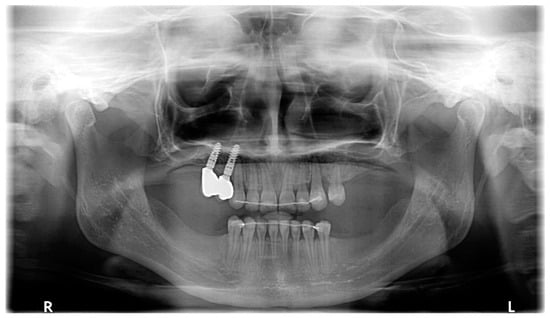

| March 2020 | The correct position of UL3; tooth no. 24 showed significant mobility; control panoramic X-ray: root resorption of tooth no. 24 (Figure 7); no possibility to conduct control visits on a regular basis due to COVID-19 pandemic—next appointment took place in November 2020. |

| August 2021 | Open sinus lift surgery with porcine bone-derived grafting material (The Graft™ bone substitute cancellous granules (Purgo Biologics, Seongnam, Republic of Korea) and BioCover™ resorbable collagen membrane (Purgo Biologics, Seongnam, Republic of Korea)) was performed on the right side of the maxilla. |

| March 2022 | Two dental implants were placed: tooth no. 14—Axiom® PX 3.4 × 12 mm (Anthogyr, Sallanches, France), tooth no. 15—Axiom® PX 3.4 × 10 mm (Anthogyr, Sallanches, France). |

| May–August 2022 | Finishing; control panoramic X-ray (Figure 8); 1st canine relationships and midline consistency; debonding of the brackets; fixed upper and lower retainers’ placement (0.027″ × 0.011″ 8-strand braided SS), tooth no. 24 was not fixed to the retainer due to increased mobility. |